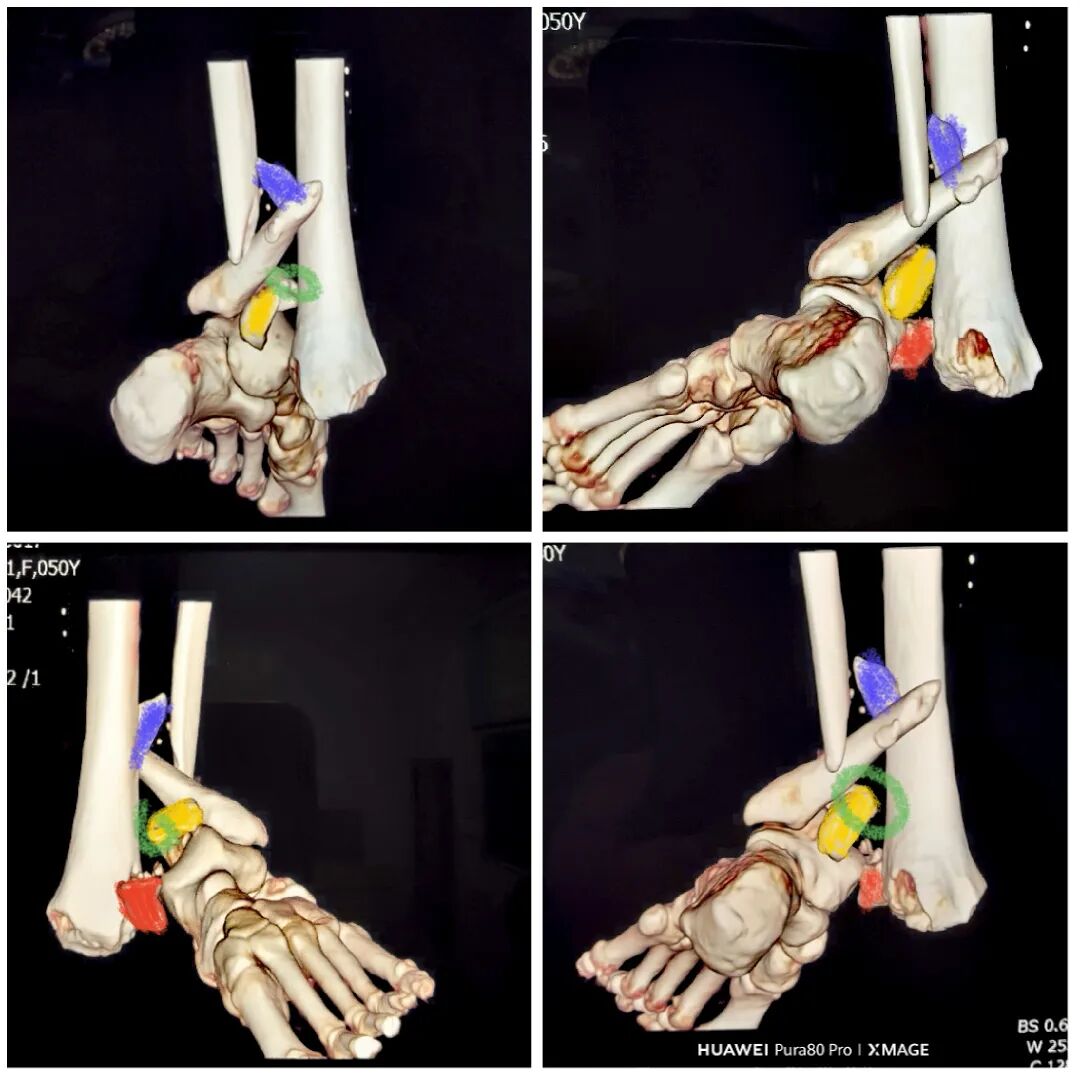

缝合前侧和后外侧切口

取外架

缝合钉道

踝关节被动活动良好

期待切口和功能的恢复